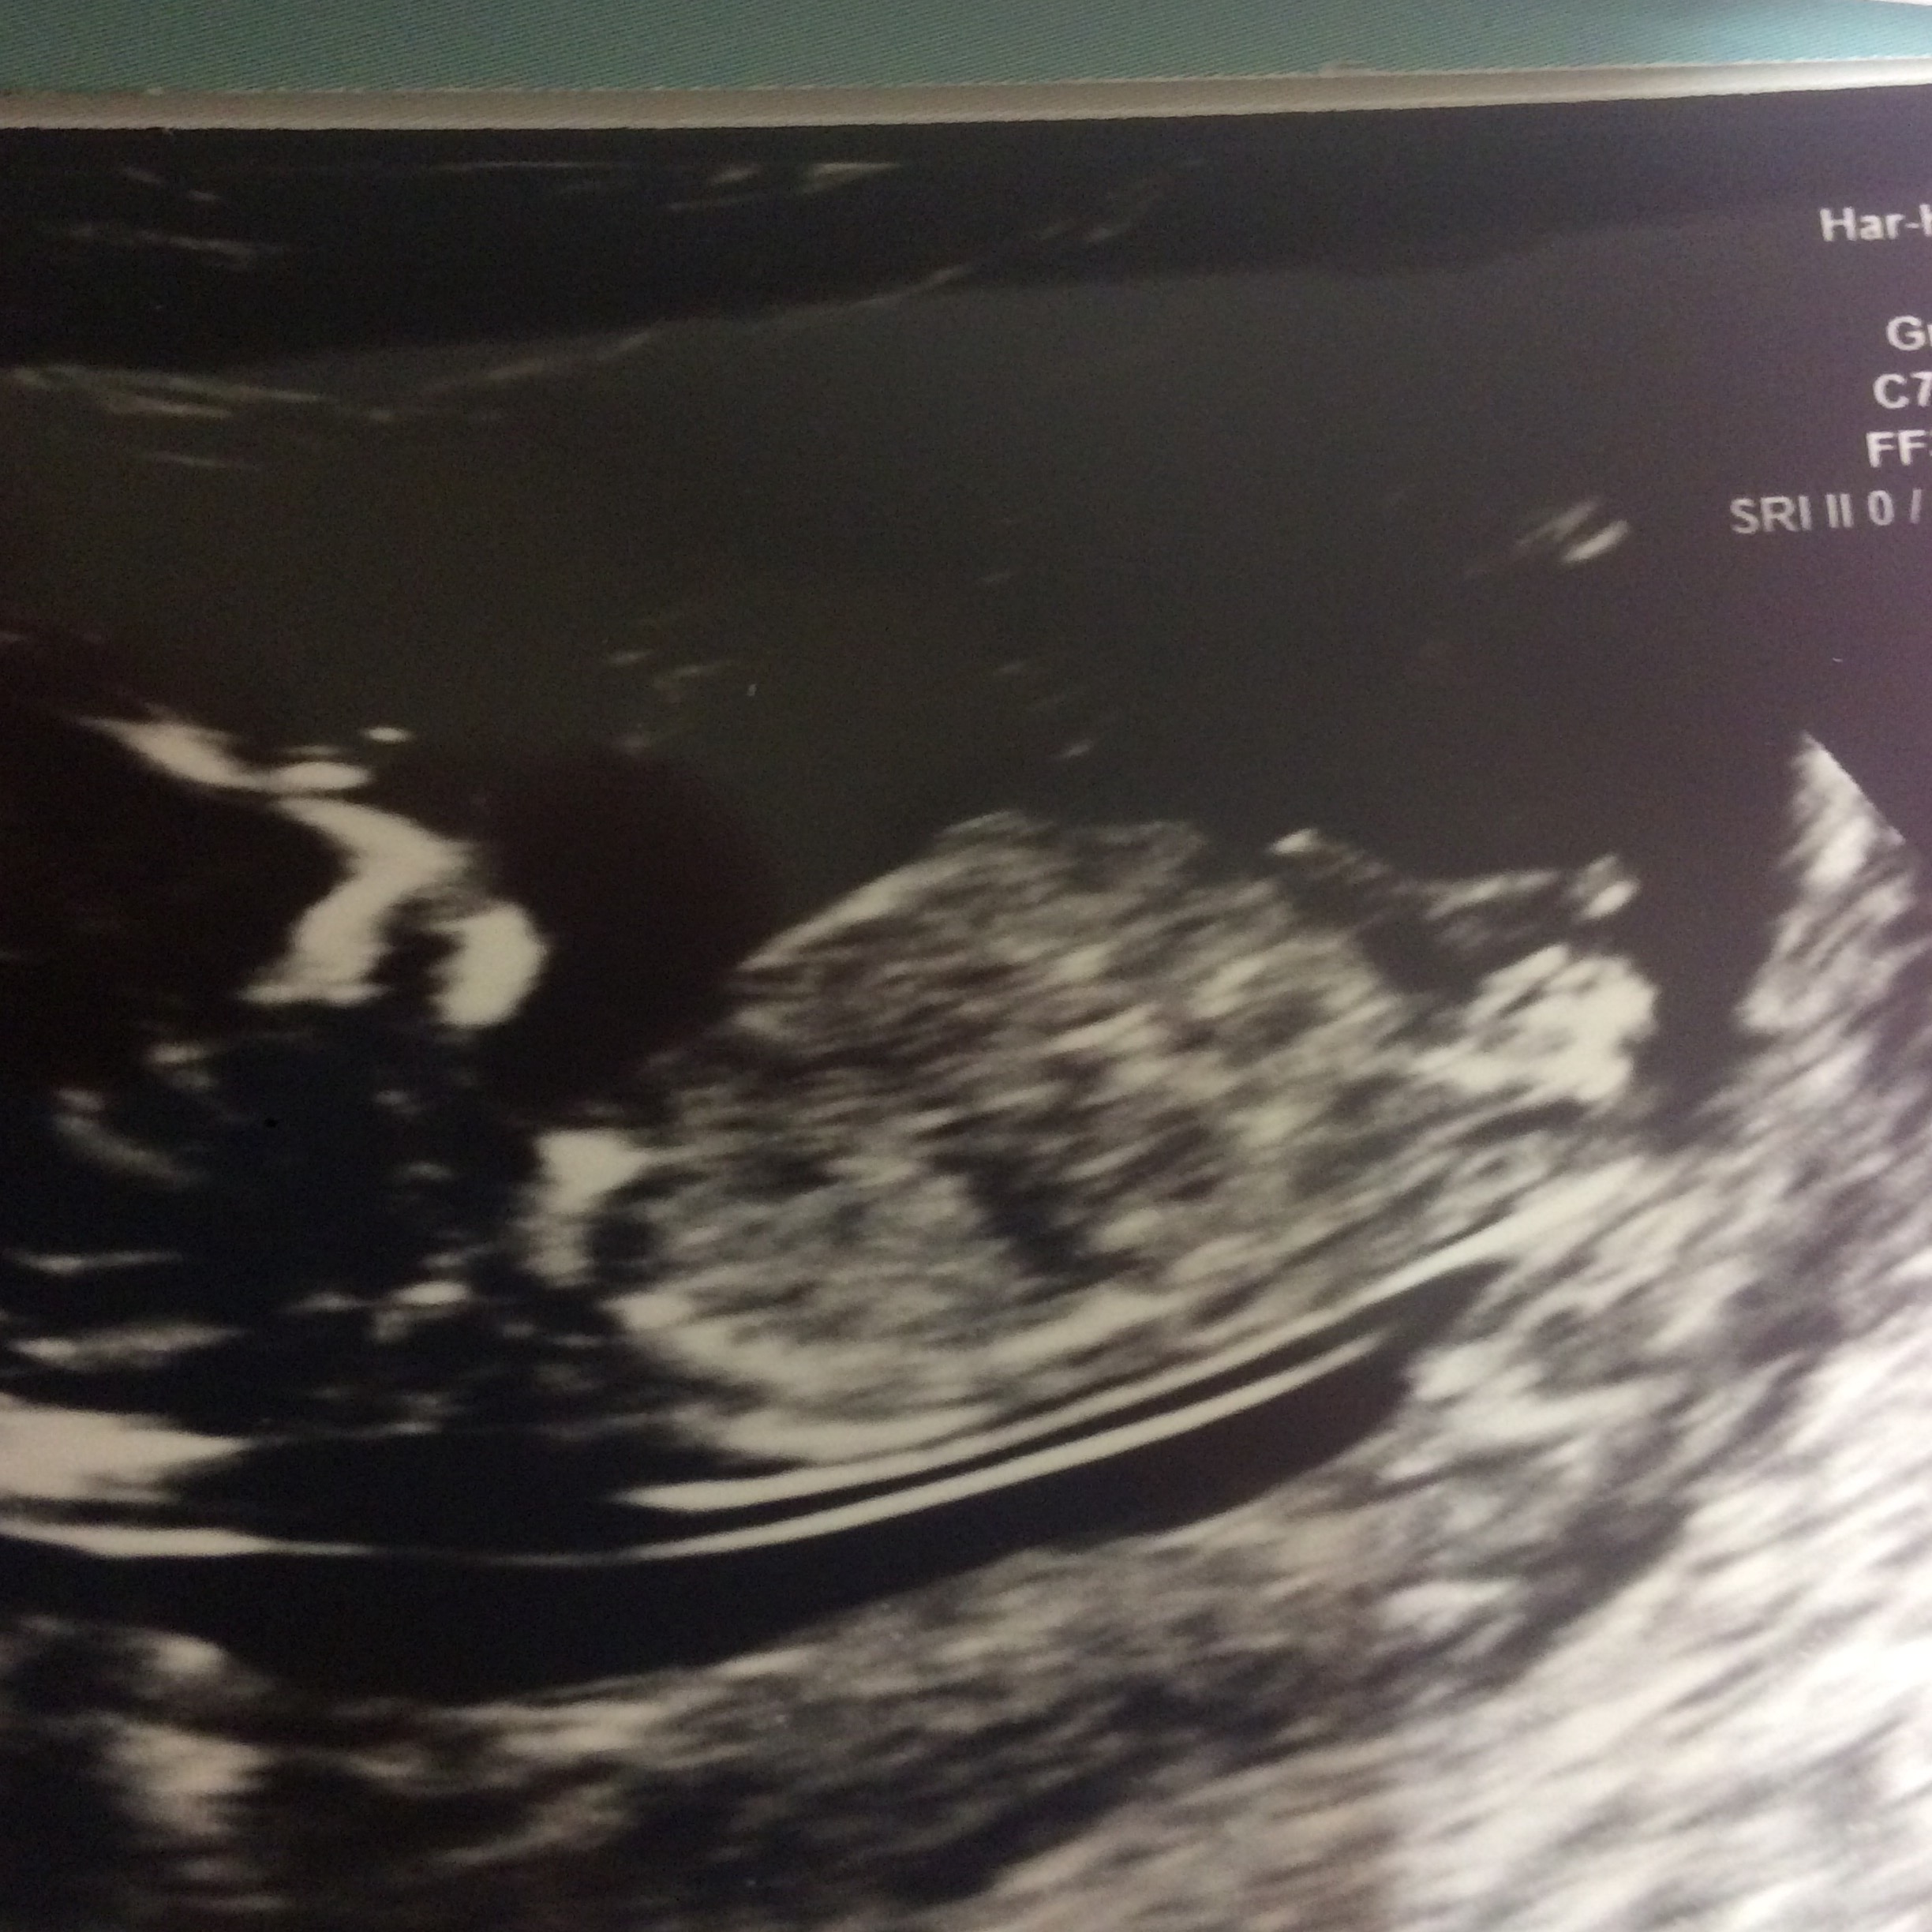

Hello. Please can anyone see the gender. Thanks xAttachment 35544Attachment 35545

girl

Girl guess from me

Thanks for looking. I have 3 boys so fingers crossed for pink xx

Looking very promising!!